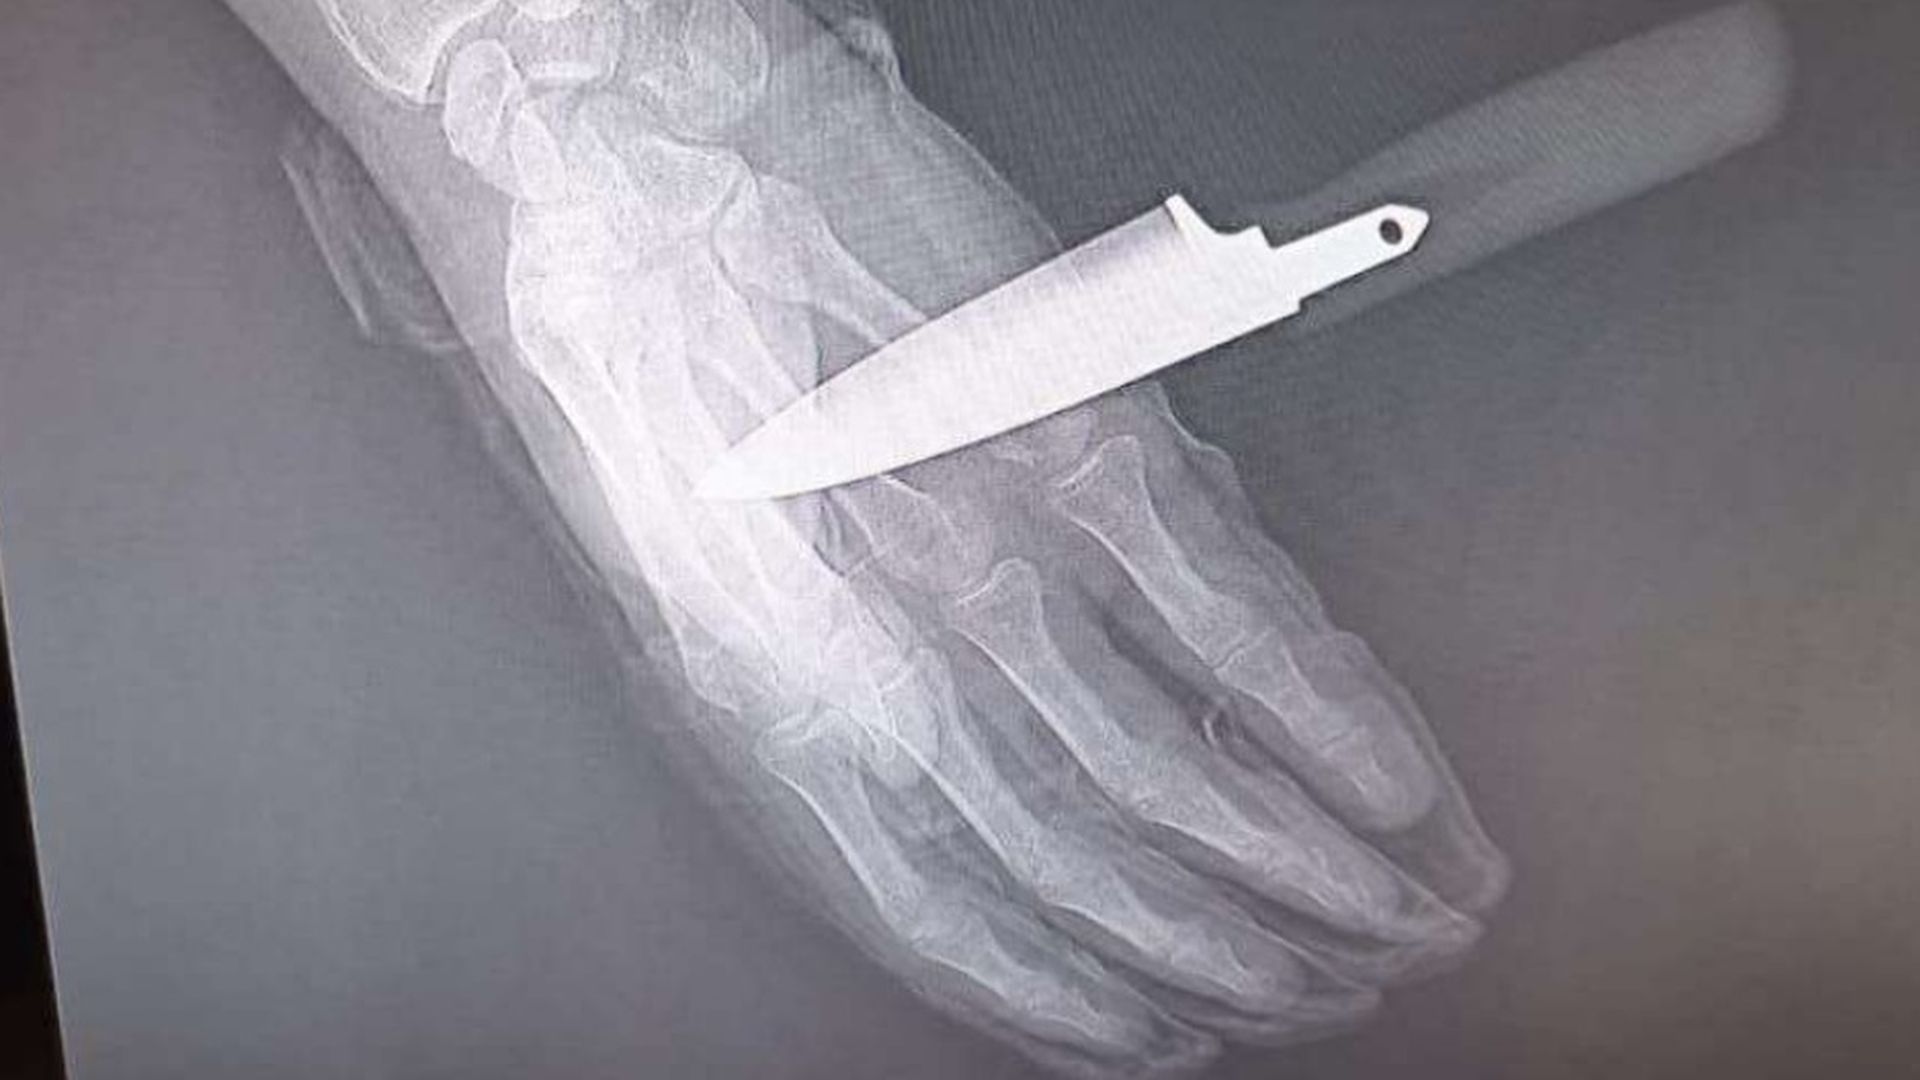

No se trataba de un golpe, sino de una puñalada, ya que el agresor portaba un cuchillo oculto. El chaleco, según el sindicato, le salvó la vida. El atacante intentó después asestarle una segunda puñalada que el policía logró repeler parcialmente, aunque el arma blanca llegó a atravesarle la mano.

No obstante, el policía pudo hacer uso de su extensible reglamentaria y, con la colaboración de una compañera, consiguió reducir y detener al agresor, mientras el agente mantenía el cuchillo clavado en la mano durante la intervención.

El agresor fue trasladado a dependencias policiales, donde continúa a la espera de pasar a disposición judicial, y el agente herido a un centro hospitalario con el cuchillo aún clavado.